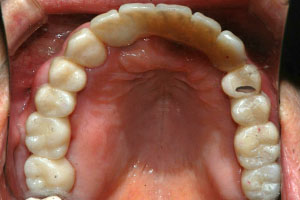

치료증례 전후사진

Before & After